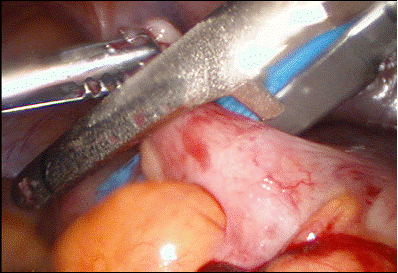

In apendicectomia asistata laparoscopic ( Ph. Mouret ) dupa ce se ligatureaza artera apendiculara si se sectioneaza mezoapendicele pe cale laparoscopica, se extrage apendicele pana la nivelul cecului ( la persoanele care au peretele slab ) si se practica dubla ligatura, sectiunea apendicelui, eventual infundarea bontului in bursa cecala si apoi introducerea cecului in interiorul cavitatii peritoneale.

Fig. 22 Apendicectomia asistata laparoscopic

Fig. 23 Apendicectomia asistata laparoscopic

Fig. 24 Apendicectomia asistata

laparoscopic